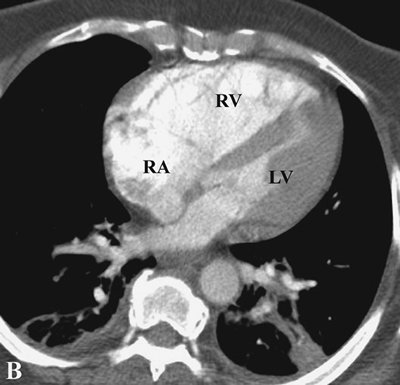

FIGURE 17-16. Chronic PE. CTPA shows enlargement of the right ventricle (RV) and right atrium (RA). The right ventricle/left ventricle (LV) ratio is greater than 1.

scintigraphy in this setting is well known. Acute embolic obstruction of a large degree of the pulmonary circulation increases pulmonary vascular resistance, leading to acute PAH. CTPA findings suggesting this complication include right ventricular enlargement (right ventricle/left ventricle ratio >1) and straightening or leftward bowing of the interventricular septum (Fig. 17-8). Pitfalls to be aware of in diagnosing PE include lymph nodes; impacted bronchi (Figs. 17-9 and 17-10); respiratory motion; vessel bifurcation; unopacified pulmonary veins (Fig. 17-11); periarterial abnormalities (lymph node enlargement or infiltration of the axial interstitium by edema fluid, inflammation, or neoplasm); pulmonary artery catheters; and pulmonary artery sarcoma (7).